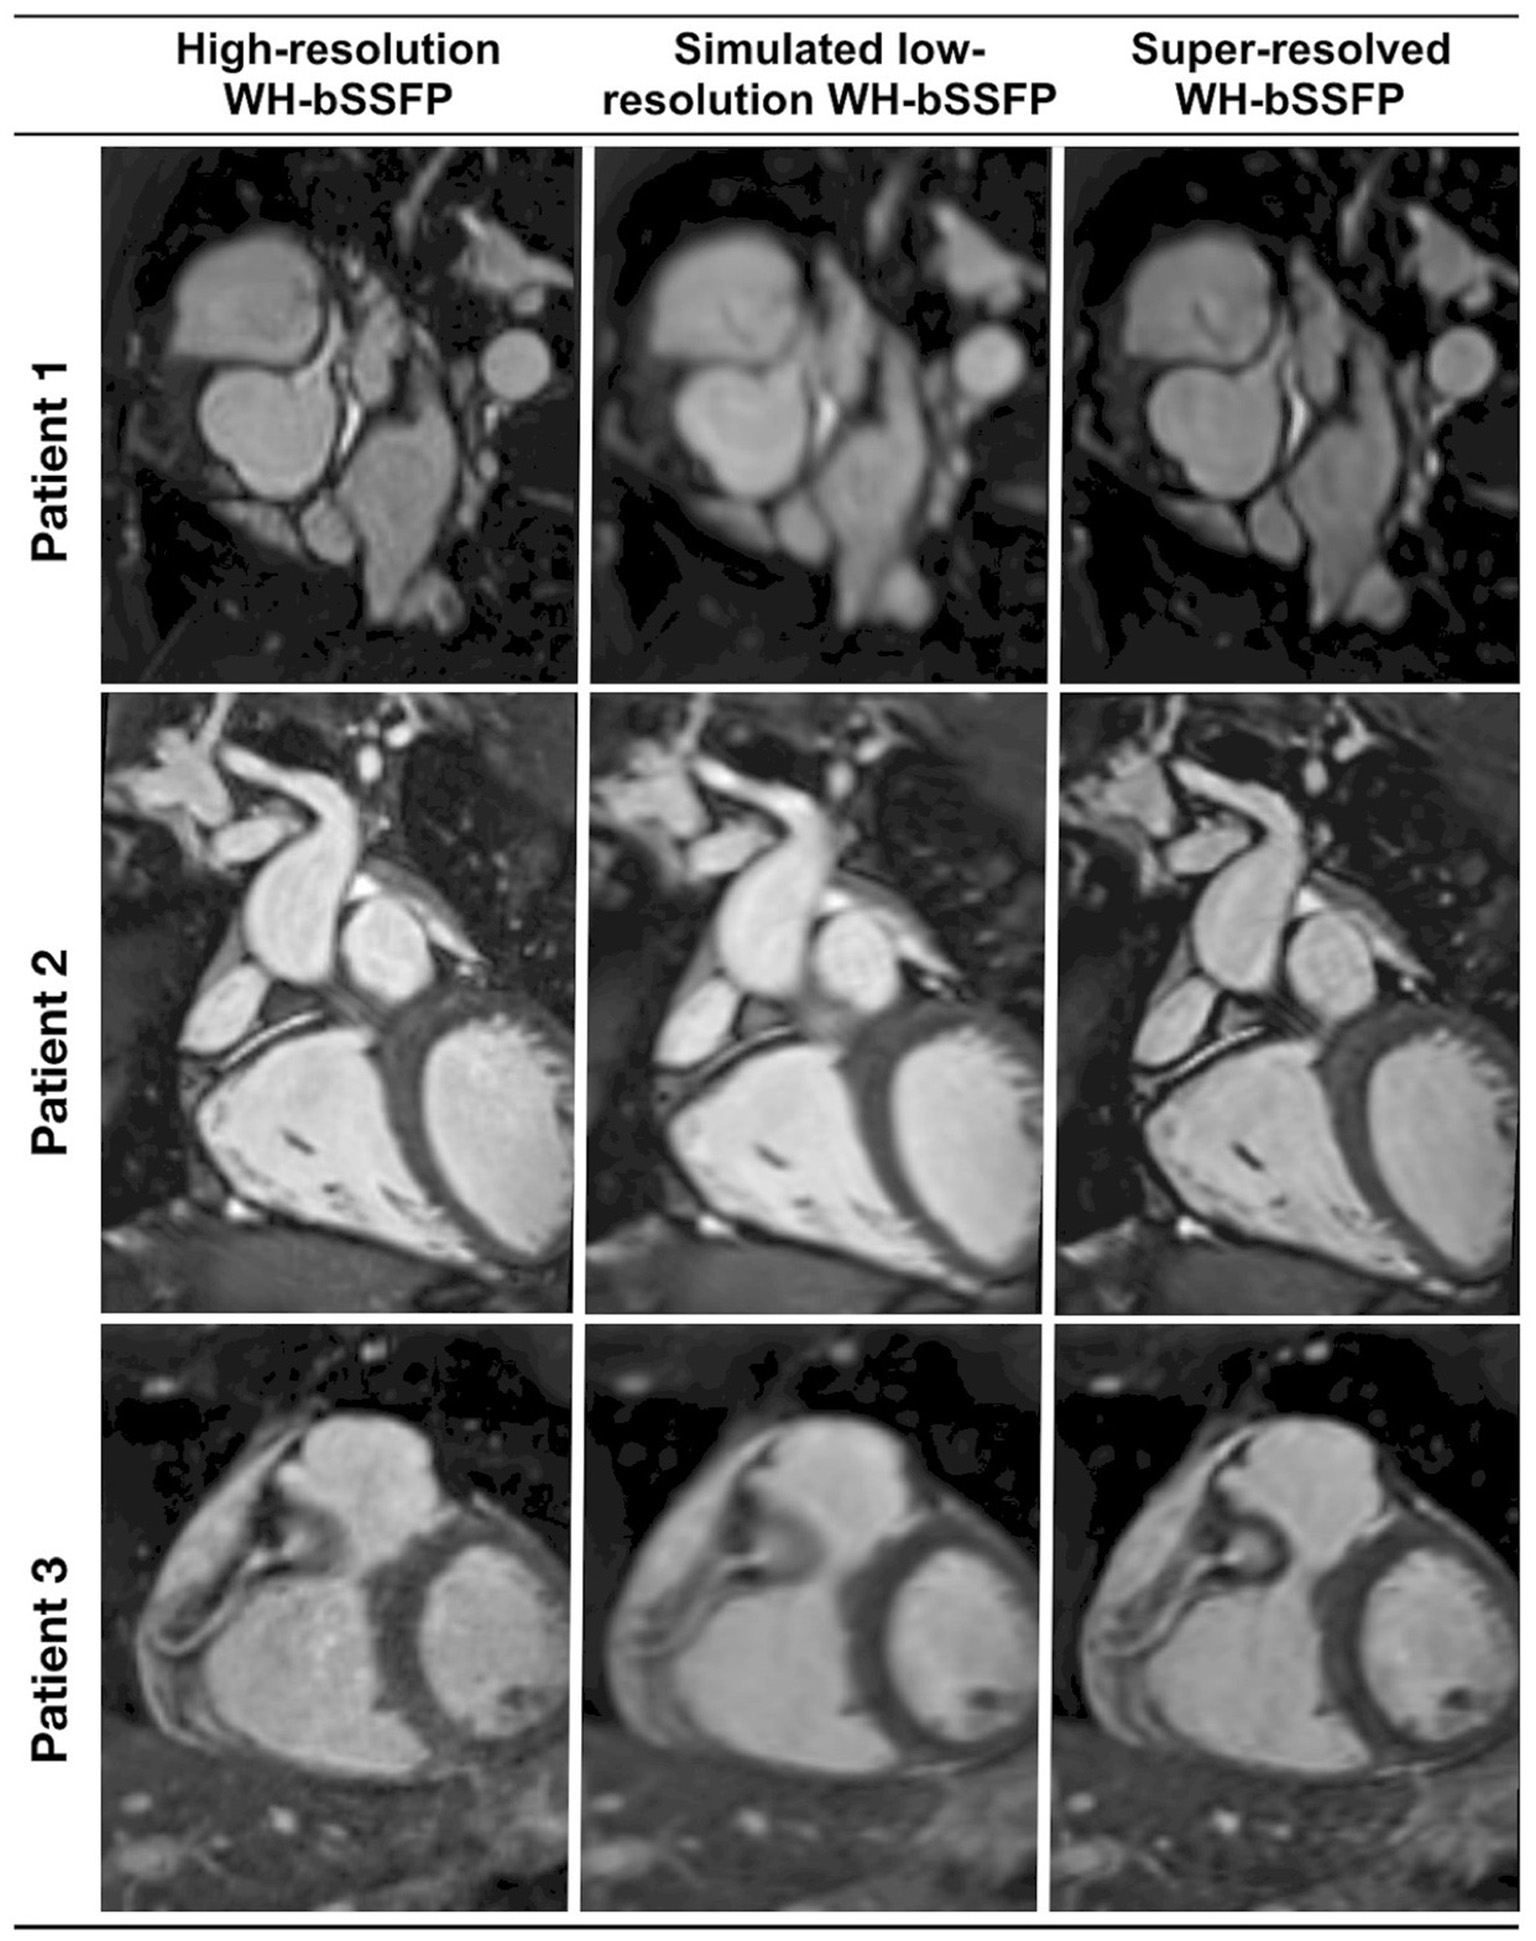

AI applications in CMR have contributed significantly to the acceleration of image acquisition and analysis. Neural networks have been applied to reconstruct data from rapidly acquired undersampled MRI images across different sequences. A deep-learning based, super-resolution CMR Angiography framework has enabled reconstruction of low resolution 1.2 x 4.8 x 4.8mm3 data acquired in 50 s scan time (11). The proposed method showed similar quantitative and perceivable image quality of the high resolution 1.2 mm3 images, achieving 16 x acceleration in acquisition time (Figure 3). Similar results have been attained with a Multi-Scale Variational Neural Network undersampled reconstruction (12), achieving 9x acceleration, in CMR Angiography 1.2 mm3 acquisition outperforming compressed sensing (CS) reconstruction. Steeden et al. (13) has successfully employed a subset of convolutional neural network, specifically the 3D residual U-net to perform super-resolution reconstruction on low-resolution three-dimensional whole heart balanced Steady State Free Precession (bSSFP) datasets, achieving similar diagnostic confidence and accuracy with high-resolution whole heart bSSFP in patients with CHD, Figure 4. Besides acquisition speed, AI has the potential to reduce breath-holds. Kuestner et al. (14) has introduced 9–15x acceleration in 3D cine images in a single 10–15 s breath hold utilising a DL-based approach. For a more detailed technical review of these methods, we refer the reader to a recent review by Alzubaidi et al. (15). Zhang et al. (16) developed an AI-based virtual native enhancement (VNE) imaging technology, using streams of CNN to employ and optimise the acquired signal from native T1 mapping and cine imaging sequences, depicting them as LGE-analogous images. This technology allows for contrast-free and efficient tissue characterisation, achieving high agreement in the quantification of tissue burden and superior image quality compared to the late gadolinium enhancement (LGE) images (see Figure 5) (16).

Figure 4. Representative image quality of the coronaries from a prospective, clinically integrated study, that utilised a residual U-Net network to facilitate super-resolution reconstruction of rapidly acquired low-resolution three-dimensional whole-heart balanced Steady State Free Precession datasets. Multi-planar reformats of the coronary artery from the respective conventional high-resolution acquisition, low-resolution acquisition, and the corresponding super-resolution reconstruction dataset. Sharpness of vascular borders is enhanced and image distortion is attenuated in the super-resolution reconstruction dataset vs. the low-resolution volume. This is particularly beneficial in the delineation of small vessels, such as the coronary arteries. Qualitative image quality analysis demonstrated no statistically significant differences between the super-resolution and the high-resolution data. Steeden et al. (13). The article is published Open Access under a CC BY licence (https://creativecommons.org/licenses/by/4.0/).